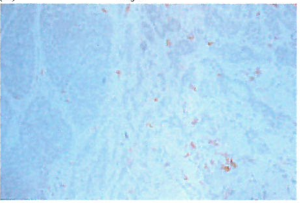

出国看病机构爱诺美康介绍,PyMT转基因小鼠体内产生的肿瘤中位点是异质性的,因为它携带一个无效的CSF-1等位甚因。用检测巨噬细胞的单克隆抗体显示肿瘤间质中存在的巨噬细胞(红褐色)。

转基因小鼠中形成的肿瘤的基因型,完全丧失CSF-1活性。因此,该小鼠的肿瘤细胞不能释放这一趋化物。在这一乳腺瘤中,几乎检测不到巨噬细胞。缺乏巨噬细胞不影响原发瘤的生长,但强烈地抑制其进展至侵袭及转移状态。